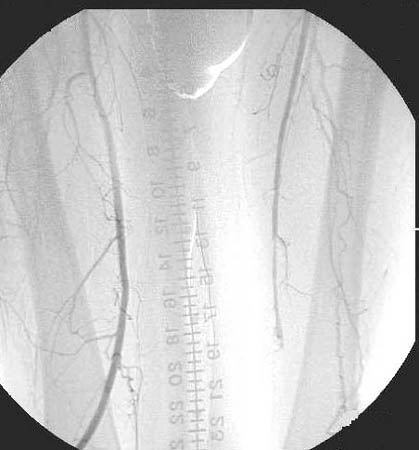

VASCULAR SURGERY  Case #6 - A 75 year old with bilateral leg crampin...    No previous image Go to next image

Arteriogram showing occlusion of the popliteal artery